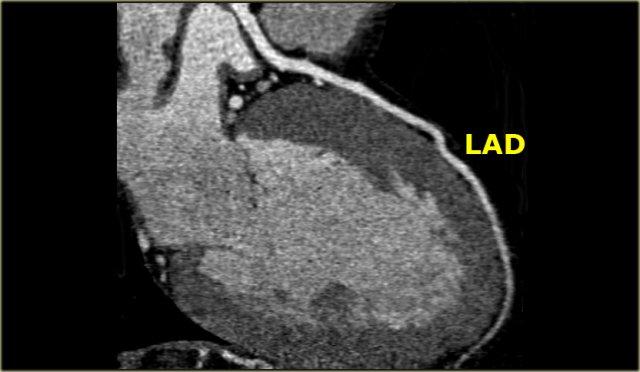

Bên trái là hình ảnh CT cắt ngang.

LCA đi giữa đường ra thất phải ở phía trước và nhĩ trái ở phía sau, rồi phân chia thành LAD và Cx.

Trên hình bên trái, chúng ta thấy thân chung động mạch vành trái phân chia thành

- Cx với nhánh bờ tù (OM)

- LAD với các nhánh chéo (DB)